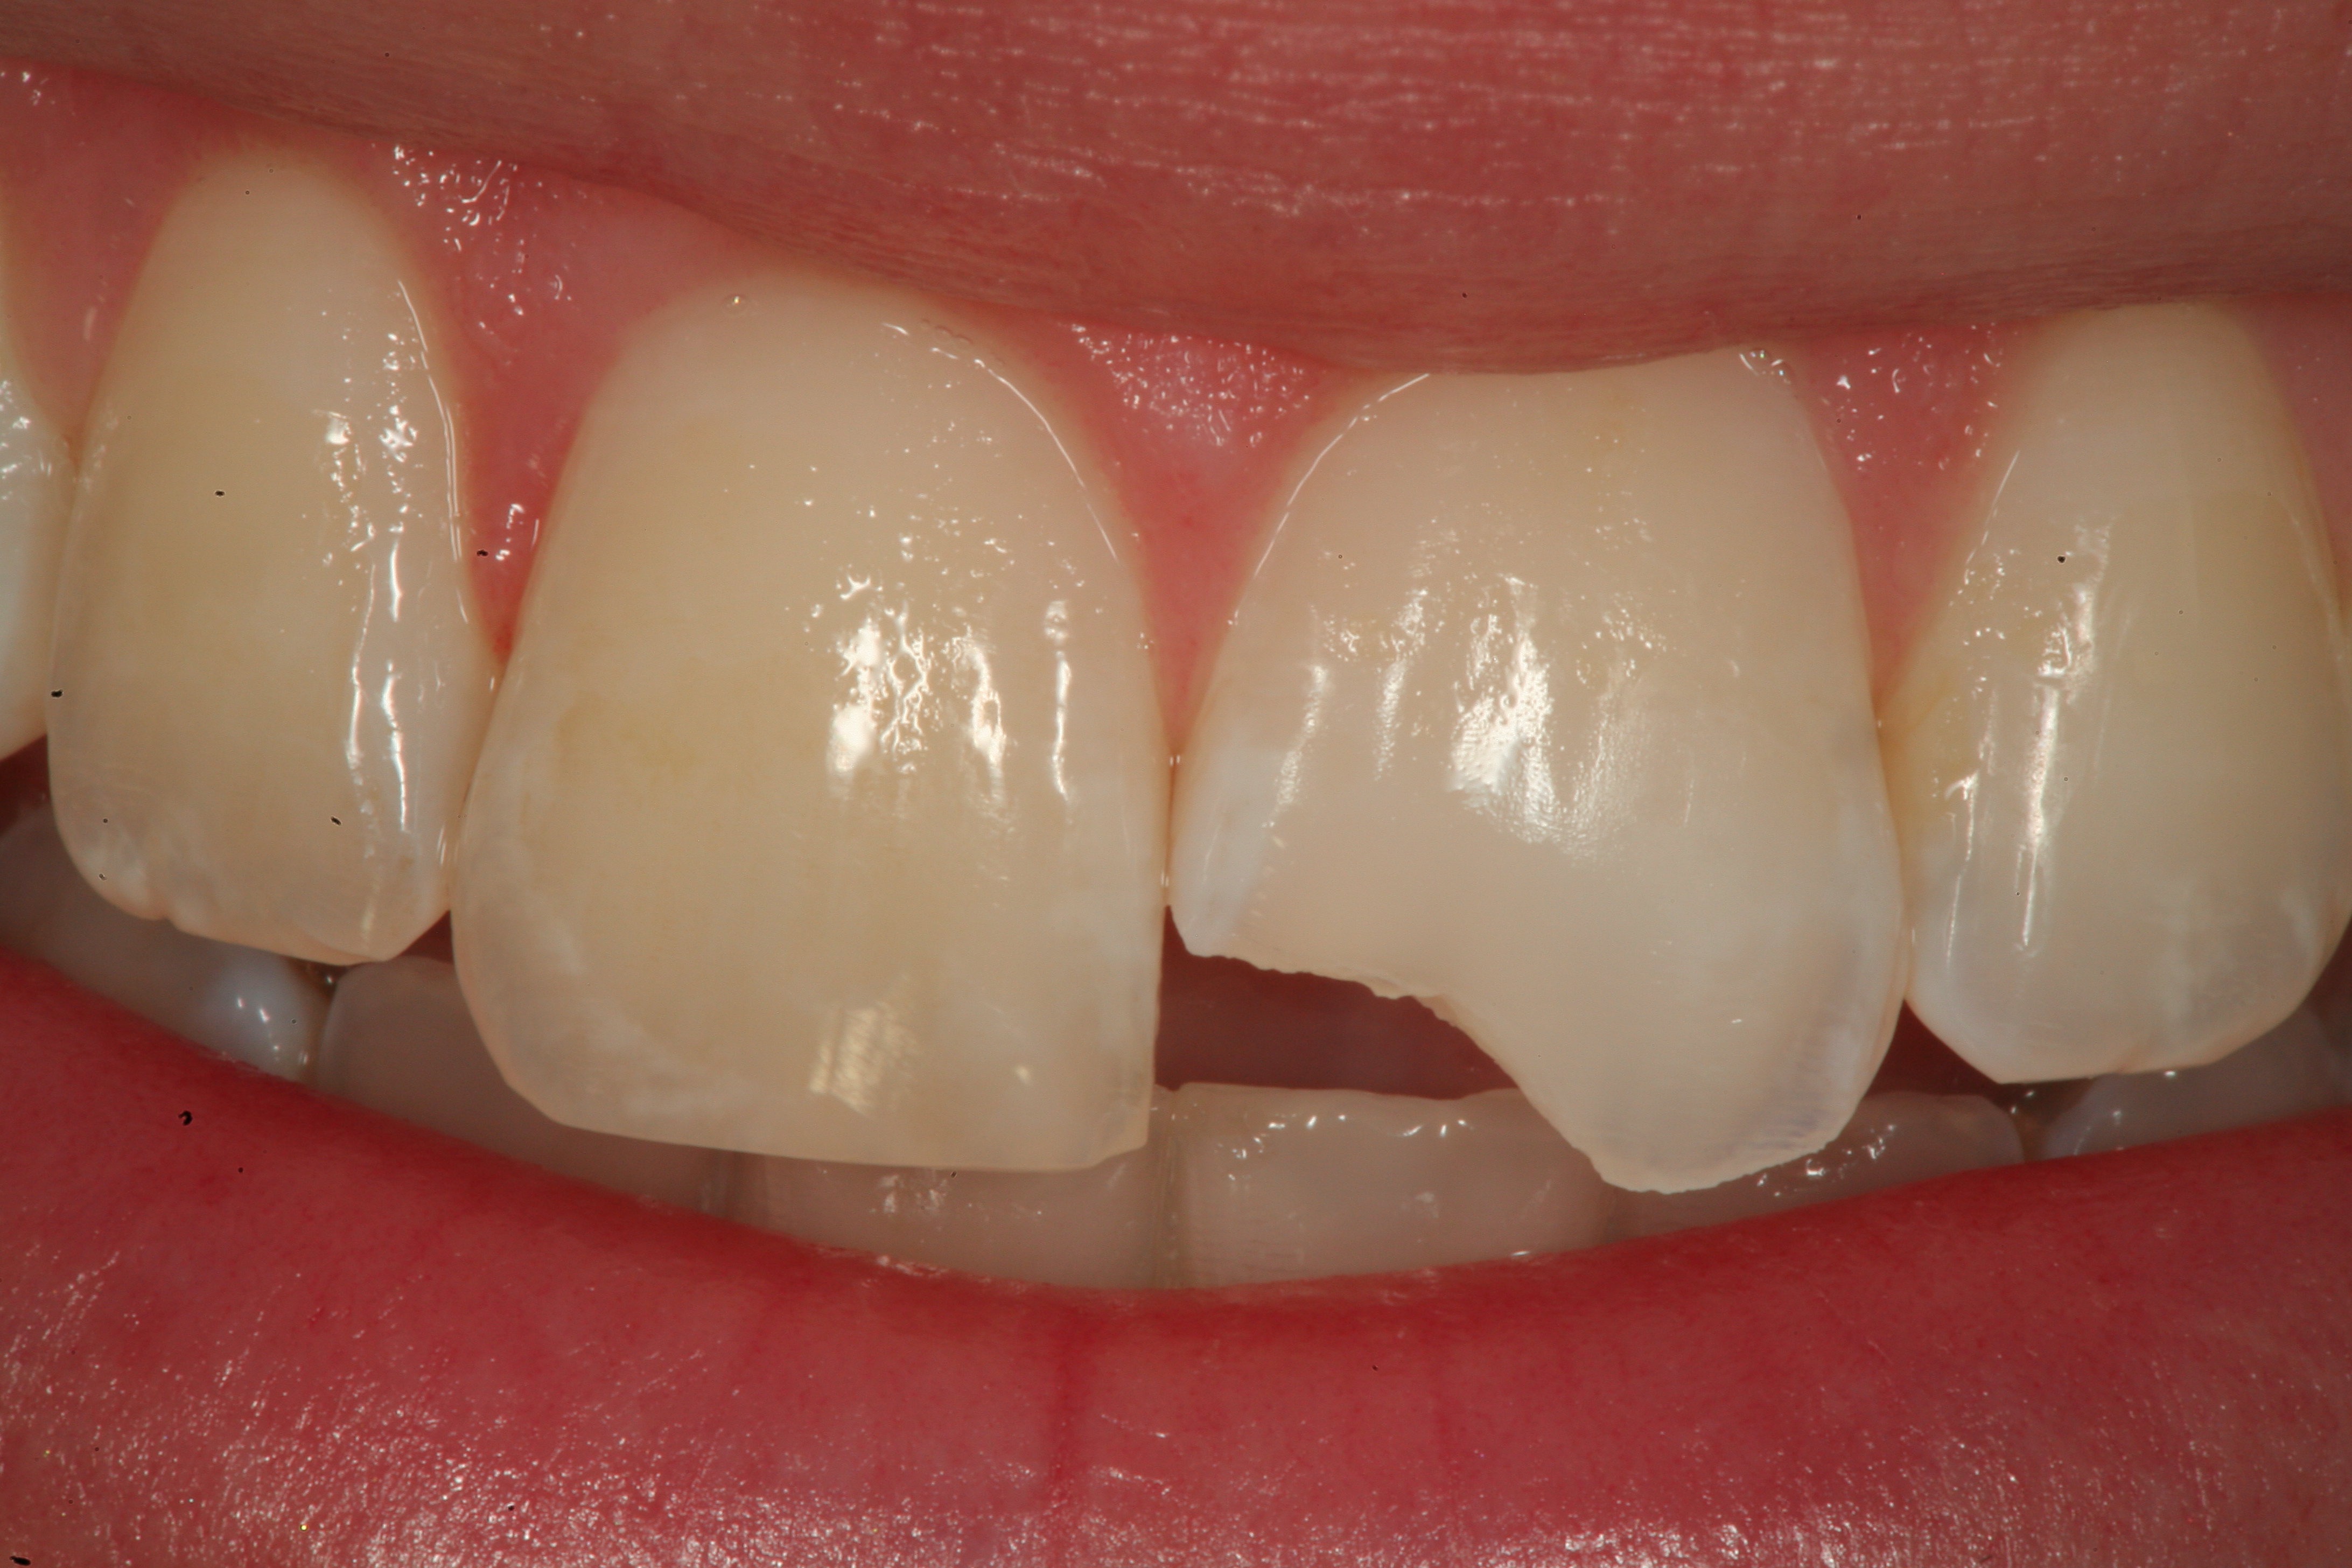

Fig 19. The completed Class IV Giomer restoration is seen on tooth No. 9 from the facial aspect. Note the esthetic quality of this layered anterior composite restoration as it compares with the surrounding natural teeth.

Figure 19